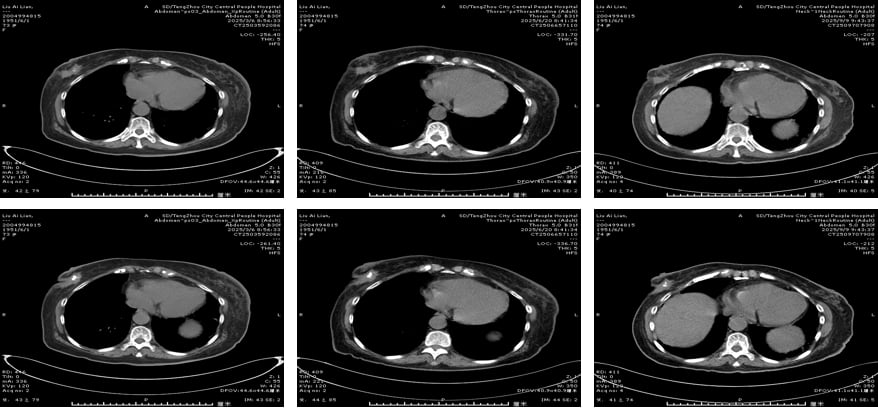

四线治疗(2024.7-2025.2):ADC药物登场,恩美曲妥珠单抗显身手

2024年7月,患者因冠心病、房性早搏就诊心内科,治疗一度中断。待心脏问题稳定后,医生引入了抗体偶联药物(ADC)——恩美曲妥珠单抗(T-DM1)。ADC药物是一种“导弹式”的精准打击武器,它将靶向抗体(如抗HER2抗体)与高效化疗药物(如DM1)偶联,通过抗体识别癌细胞表面的靶点,将化疗药物精准递送至癌细胞内部,减少对正常细胞的损伤,从而提高疗效并降低全身性副作用。经过4个周期的T-DM1治疗,患者病情稳定(SD),仅出现轻度乏力、血小板减少,耐受性良好。

五线治疗(2025.3-至今):德曲妥珠单抗持续抗癌,疗效显著

2025年3月,患者开始接受目前最先进的ADC药物之一——德曲妥珠单抗(T-DXd)治疗。德曲妥珠单抗同样是ADC药物,它将抗HER2抗体与拓扑异构酶I抑制剂偶联,具有更高的药物抗体比(DAR),意味着每个抗体携带的化疗药物更多,且其化疗载荷在肿瘤微环境中释放后,还能穿透细胞膜,对周围的癌细胞产生“旁观者效应”,进一步增强抗肿瘤活性。截至目前,患者已接受9个周期的T-DXd治疗,左侧腋窝淋巴结较前变小,左乳不规则软组织密度范围缩小,病情持续稳定,且不良反应轻微,耐受性良好。这再次证明了新一代ADC药物在HER2阳性乳腺癌后线治疗中的卓越疗效和安全性。